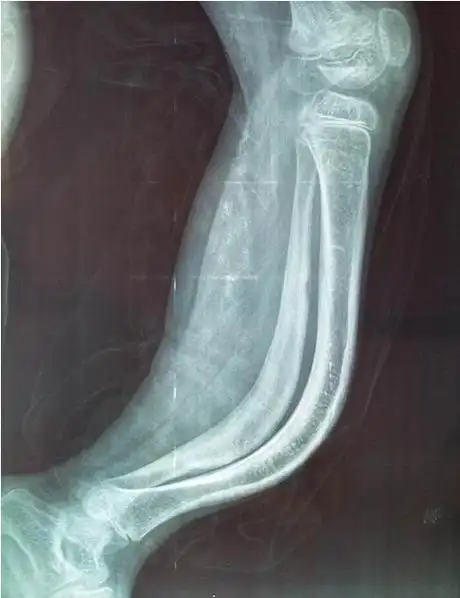

胳膊骨折,医生却说不用管,青枝骨折是个很特